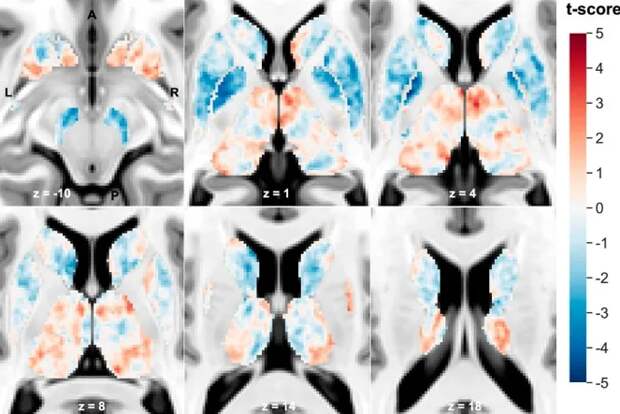

Эти аномалии были особенно выражены в глубоких структурах мозга, таких как хвостатое ядро, скорлупа и бледный шар, которые вместе играют важную роль в контроле движений, эмоций и сложных форм поведения.

Карта t-оценки подкорковой магнитной восприимчивости (χ) на Т1-взвешенном шаблоне Монреальской неврологической визуализации (MNI) на уровне и ориентации аннотированного среза.